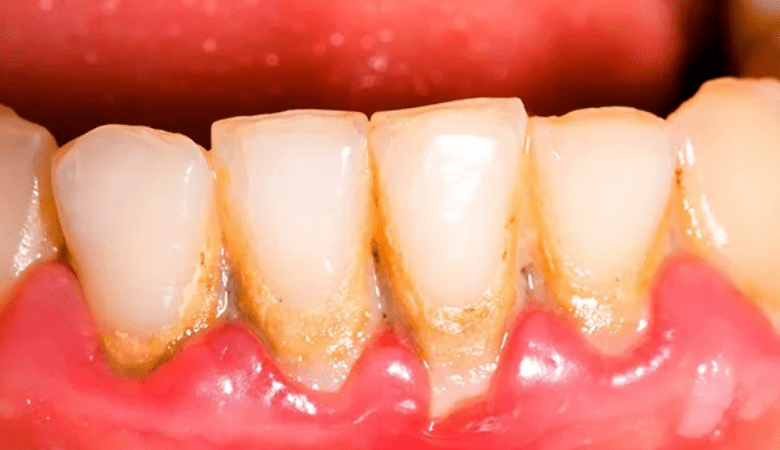

Hình ảnh viêm nướu răng

Quá nhiều cao răng lâu ngày gây viêm nướu răng (Nguồn: Internet)